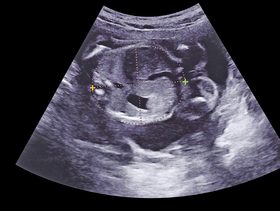

الاسبوع الثامن عشر وأبرز النصائح والعوارض والمعلومات التي على كل حامل معرفتها في هذه المرحلة تجدينها في مجموعة من المواضيع على عائلتي